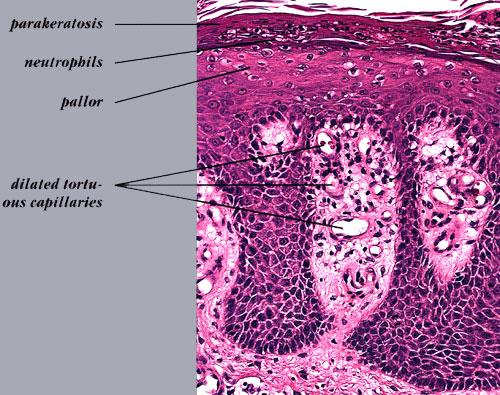

The earliest pinhead-sized macules or smooth-surfaced papules show subtle histologic changes with a preponderance of dermal changes . At first, there is capillary dilation and edema in the papillary dermis, with a lymphocytic infiltrate surrounding the capillaries. The lymphocytes extend to the lower portion of the epidermis, where slight spongiosis develops. Then focal changes occur in the upper portion of the epidermis, where granular cells become vacuolated and disappear, and mounds of parakeratosis are formed. Neutrophils are usually seen only at the summits of some of the mounds of parakeratosis and appear scattered through an otherwise orthokeratotic cornified layer . These mounds of parakeratosis with neutrophils represent the earliest manifestation of Munro microabscesses . At this stage, which is characterized clinically by an early scaling papule, a histologic diagnosis of psoriasis can often be made. In some cases, when there is marked |

exocytosis of neutrophils, they may aggregate in the uppermost portion of the spinous layer to form small spongiform pustules of Kogoj. Lymphocytes remain confined to the lower epidermis, which, as more and more mitoses occur, becomes increasingly hyperplastic. The epidermal changes are at first focal, but later become confluent, leading clinically to plaques. In the fully developed lesions of psoriasis, as best seen at the margin of enlarging plaques, the histologic picture is characterized by (a) acanthosis with regular elongation of the rete ridges with thickening in their lower portion; (b) thinning of the suprapapillary epidermis with the occasional presence of small spongiform pustules; (c) pallor of the upper layers of the epidermis; (d) diminished to absent granular layer; (e) confluent parakeratosis; (f) the presence of Munro microabscesses; (g) elongation and edema of the dermal papillae; and (h) dilated and tortuous capillaries . |

Munro microabscesses are located within the parakeratotic areas of the cornified layer . They consist of accumulations of neutrophils and pyknotic nuclei of neutrophils that have migrated there from capillaries in the papillae through the suprapapillary epidermis. As a rule, Munro microabscesses are easily found in early lesions but are few in number or absent in longstanding lesions . The dermal papillae, in accordance with the elongation and basal thickening of the rete ridges, are elongated and club shaped. They show edema, and the capillaries within them appear dilated and tortuous. A relatively mild inflammatory infiltrate is present in the upper dermis and the papillae. It consists of lymphocytes, except in early lesions, in which neutrophils are also present in the upper portion of the papillae . |